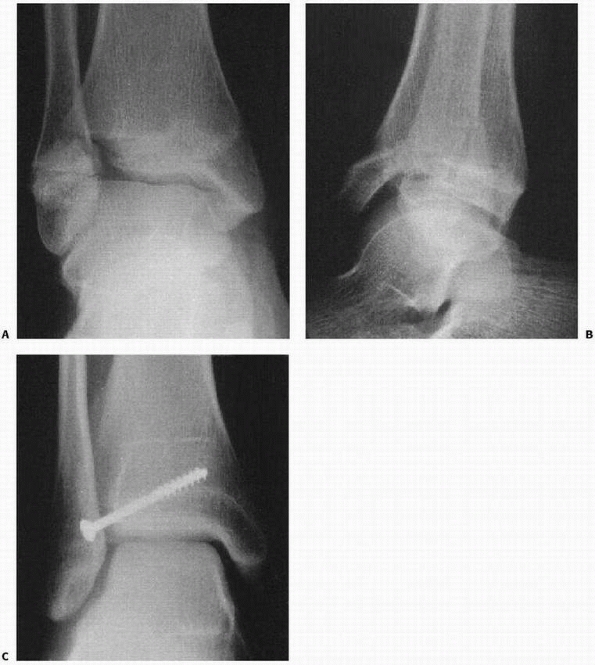

![]() |

FIGURE 26-2

Comminuted Salter-Harris type IV fracture of the distal tibia and displaced Salter-Harris type I fracture of the distal fibula produced by an inversion (shearing) mechanism in a 10-year-old girl. |

-

Grade I: The adduction or inversion force

avulses the distal fibular epiphysis (Salter-Harris type I or II

fracture). Occasionally, the fracture is transepiphyseal; rarely, the

lateral ligaments fail. -

Grade II (Fig. 26-4):

Further inversion produces a tibial fracture, usually a Salter-Harris

type III or IV and rarely a Salter-Harris type I or II injury, or the

fracture passes through the medial malleolus below the physis (Fig. 26-5).